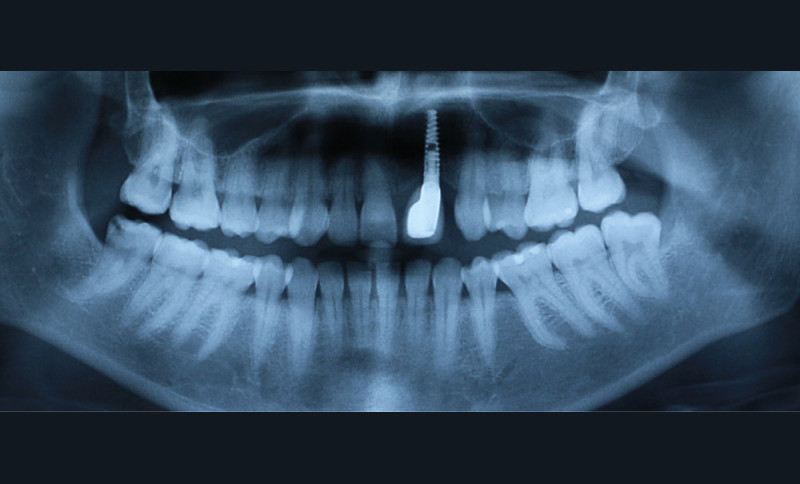

À la suite d’un accident de la voie publique il y a plusieurs années, le secteur antérieur maxillaire a été traumatisé, 21 et 22 ont été expulsées, et 11 et 12 présentent d’importantes résorptions radiculaires externes inflammatoires visibles à la radiographie panoramique (fig. 1).

- au niveau dentaire : une arcade maxillaire asymétrique avec déviation du milieu maxillaire à gauche. On note l’absence de 21, 22, 25, 35 et 45, une classe II droite et gauche avec infraclusion antérieure et la présence d’un implant en place de 21 avec un diastème de 3 mm entre 21 et 23 (fig. 3) ;